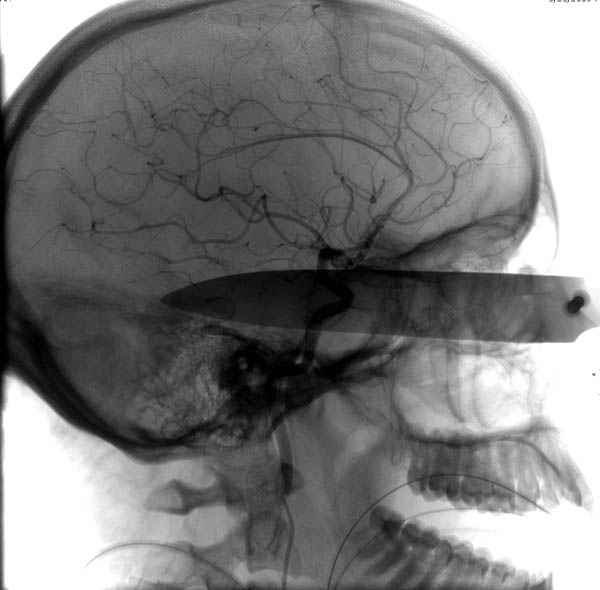

В своих выступлениях я рассказывал, что наши центры в мирное время по пенетрирующим травмам не уступает Ираку или Афганстану, и вот недавно к нам поступила больная 22 лет, травма "ножом в глаз" от бывшей подруги нынешнего "бой френда".

При поступлении в сознании, жаловалась на неприятные ощущения в глазнице.

По протоколу сделаны все необходимые исследования: рентген, ангиограмма с 3Д реконструкцией, где обнаружили что все жизненно важные сосуды не задеты, даже некоторые "сидят" изгибаясь на ноже.